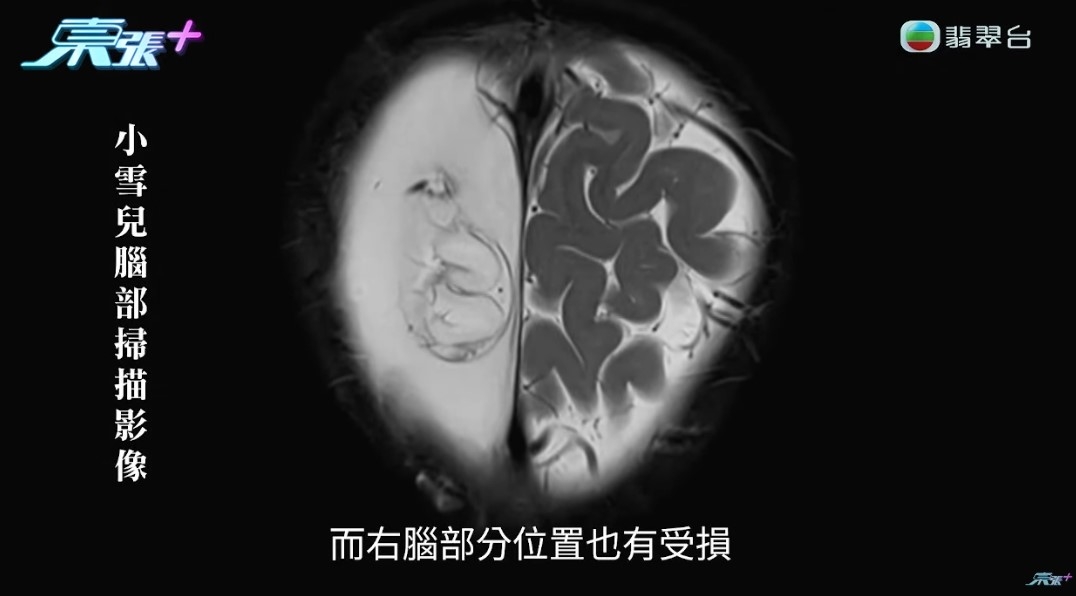

出事後,其實小雪兒的智能、學習能力都嚴重受損,聽醫生描述小雪兒大腦狀況,實在令人心傷,「醫生就話個腦本來一個氣球脹卜卜,但而家漏曬氣,得翻個殘渣喺入邊,即是,沒有了。右腦部分位置都受損,但醫生期望右邊腦未來可以取代左邊,我地就抱住呢個盼望,希望右邊真係可以做埋左邊的功能,將個不便減到最低!」